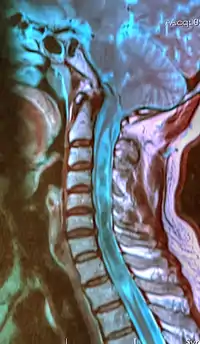

A sagittal FLAIR MRI scan, from a patient with an Arnold–Chiari malformation, demonstrating tonsillar herniation of 7 mm.

Diagnosis is made through a combination of patient history, neurological examination, and medical imaging.[20][21] Magnetic resonance imaging (MRI) is considered the preferred imaging modality for Chiari malformation.[22] The MRI visualizes neural tissue such as the cerebellar tonsils and spinal cord as well as bone and other soft tissues. CT and CT myelography are other options and were used prior to the advent of MRI, unfortunately the resolution of CT based modalities do not characterize syringomyelia and other neural abnormalities as well.[23]

By convention, the cerebellar tonsil position is measured relative to the basion-opisthion line, using sagittal T1 MRI images or sagittal CT images.[24] The selected cutoff distance for abnormal tonsil position is somewhat arbitrary, as not every person will be symptomatic at a certain amount of tonsil displacement, and the probability of symptoms and syrinx increases with greater displacement; however, greater than 5 mm is the most frequently cited cutoff number, though some consider 3–5 mm to be "borderline"; pathological signs and syrinx may occur beyond that distance.[24][25][26] One study showed little difference in cerebellar tonsil position between standard recumbent MRI and upright MRI for patients without a history of whiplash injury.[18] Neuroradiological investigation is used to first rule out any intracranial condition that could be responsible for tonsillar herniation. Neuroradiological diagnostics evaluate the severity of crowding of the neural structures within the posterior cranial fossa and their pressure against the foramen magnum. Chiari 1.5 is a term used when both brainstem and tonsillar herniation through the foramen magnum are present.[27]